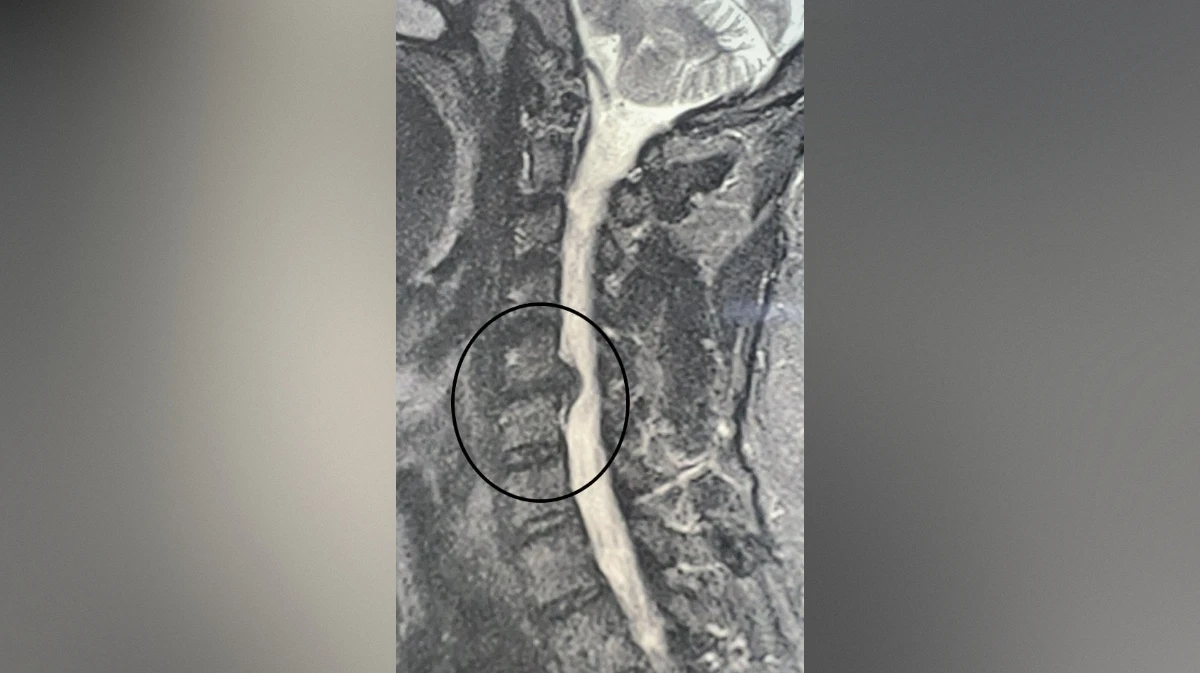

В Воронеже хирурги городской клинической больницы №11 спасли руку пациенту с грыжей. В конце октября в больницу обратился 49-летний мужчина, у которого месяц болела шея. Кроме того, пациент жаловался на онемение и слабость в правой руке. Ранее мужчина проходил лечение, но оно не помогло. Врачи обнаружили грыжу, спондилоартроз (поражение межпозвонковых суставов, которое затрагивает хрящи, костные ткани, связки и околосуставные мышцы. – Прим. ред.) и радикулит. Без удаления грыжи у пациента мог развиться паралич правой руки, поэтому было принято решение провести операцию. Об этом сообщили в пресс-службе министерства здравоохранения Воронежской области во вторник, 18 ноября.

Нейрохирурги Владимир Дронов и Евгений Дронов удалили межпозвонковый диск и грыжу с использованием операционного оптического прибора, микрохирургической техники и инструментария. Помимо этого, была устранена компрессия спинного мозга и нервных корешков, а также установлен межтеловой кейдж – металлическая конструкция, которая размещается между двумя соседними позвонками и соединяет их между собой.